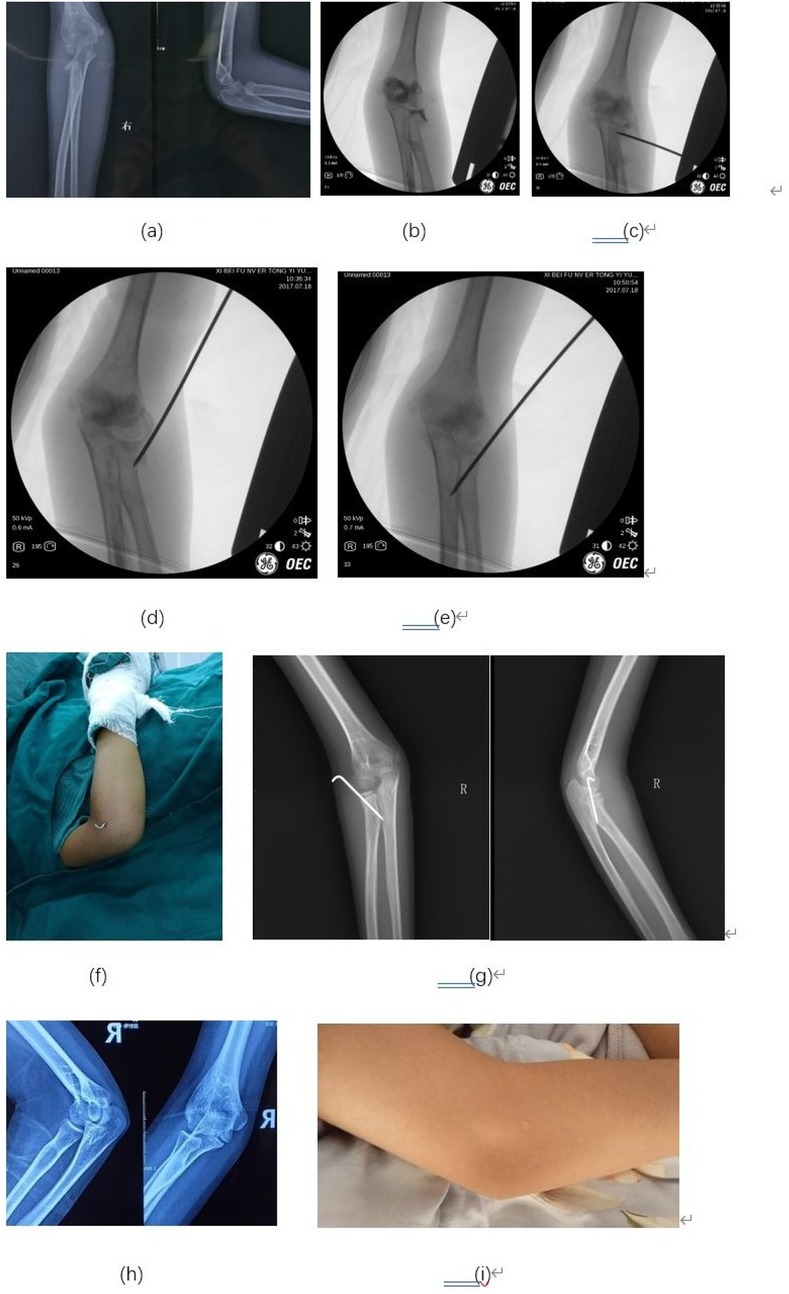

According to the Metaizeau reduction classification (14), 42 cases were rated as excellent, and five cases were rated as good (Table 3). Based on the Metaizeau clinical classification (15), 45 cases were excellent, and two cases were good. All the patients had a good function of the affected elbow (Table 4). The flexion and extension of the affected elbow was normal. There was no limitation of the pronation and supination function of the affected forearm. No patient needed to be operated again. A typical case with an excellent postoperative outcome is illustrated in Figures 2a–f.

Figure 2. Typical case: An 8-year-old girl presented with a right elbow injury. (a) The preoperative x-ray showed 62° angulation of the radial neck fracture. (b) Arthrography provided clearer visualization of the radial neck angulation, more accurately delineating the fracture extent. (c) A 2.0 mm K-wire was inserted laterally and positioned distal to the fracture site. (d) Leverage reduction was performed using the K-wire to realign the fracture fragments. (e) The K-wire was further advanced to penetrate the cortex, providing additional stability to the reduced fracture. (f) The external portion of the K-wire was carefully removed, ensuring secure fixation while minimizing soft tissue irritation. (g) Anteroposterior (AP) and lateral projection (LP) x-rays taken one month postoperatively demonstrated successful union of the fracture. (h) AP and lateral x-rays at 7.5 years demonstrated excellent humeroradial and proximal radioulnar congruity, confirming long-term stability. (i) At 7.5 years, only a faint scar remains on the lateral elbow, yielding minimal cosmetic impact.